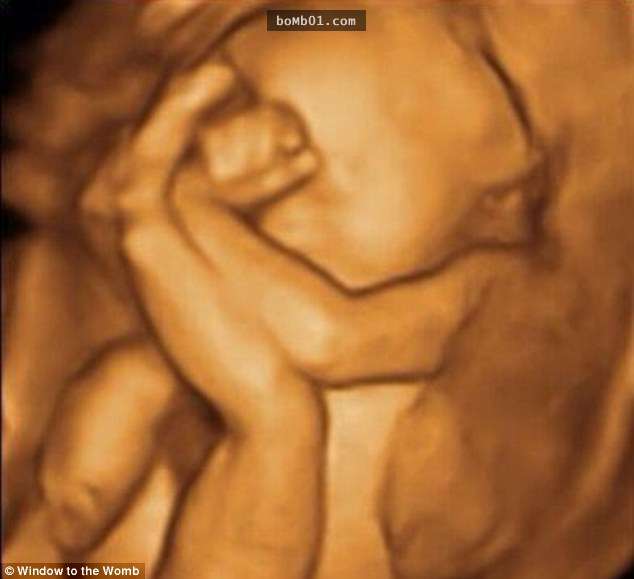

▼這個寶寶不願意父母太早看到自己,所以將臉埋在手臂中。